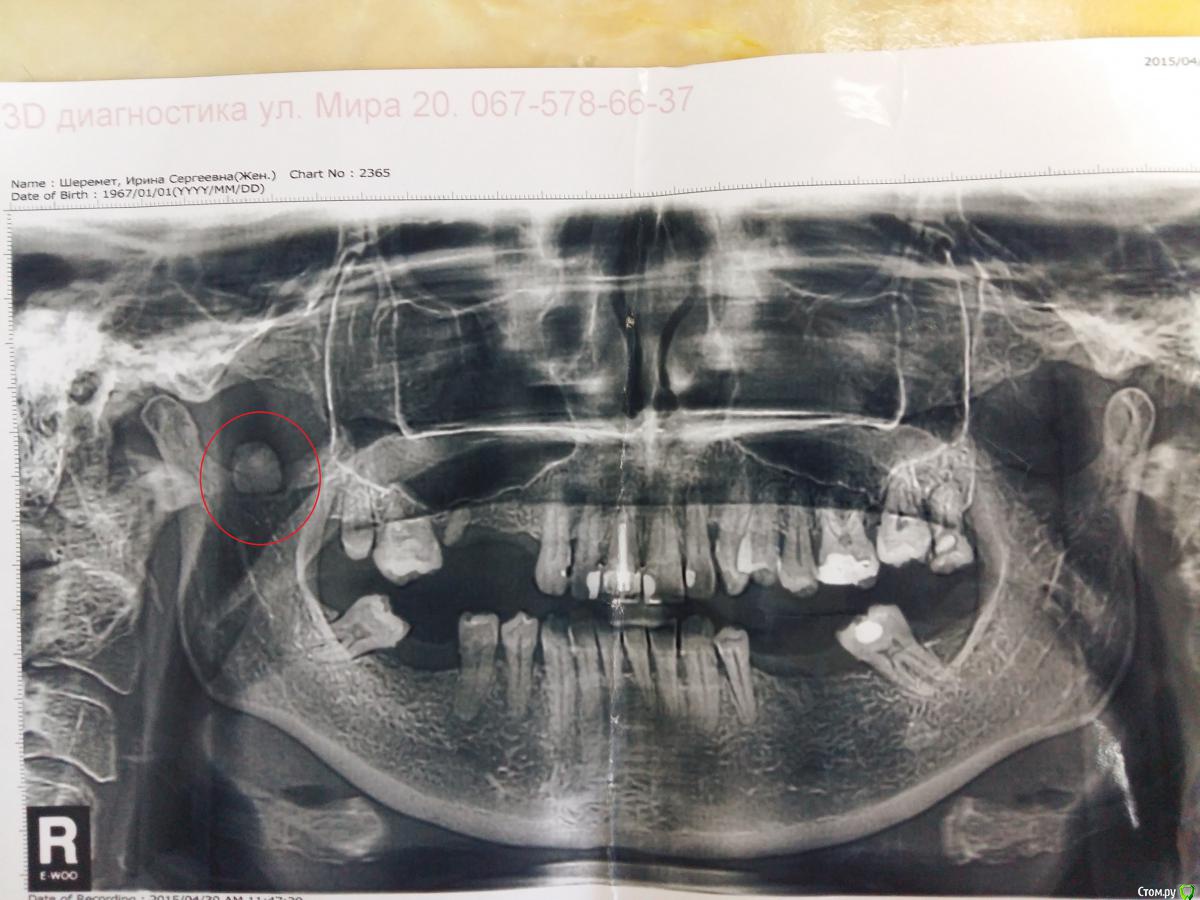

Kostoprav Опубликовано 24 мая, 2015 Поделиться Опубликовано 24 мая, 2015 пациентка явилась с целью санации, принесла панорамный снимок.как думаете что это, может просто артефакт? Ссылка на комментарий

умножающий печаль Опубликовано 25 мая, 2015 Поделиться Опубликовано 25 мая, 2015 Скорее всего наложился зуб II шейного позвонка. 1 Ссылка на комментарий

zzkz Опубликовано 26 мая, 2015 Поделиться Опубликовано 26 мая, 2015 Скорее всего наложился зуб II шейного позвонка.мне кажется это должно быть тогда и с другой стороны, симметрично. не так ли? Ссылка на комментарий

Fake personage Опубликовано 26 мая, 2015 Поделиться Опубликовано 26 мая, 2015 мне кажется это должно быть тогда и с другой стороны, симметрично. не так ли?не обязательно Ссылка на комментарий

умножающий печаль Опубликовано 26 мая, 2015 Поделиться Опубликовано 26 мая, 2015 (изменено) мне кажется это должно быть тогда и с другой стороны, симметрично. не так ли?Абсолютной симметрии не добиться. Всё равно присутствует поворот или наклон головы. По-крайней мере я симметричных лиц и снимков не видел. ИМХО. Изменено 26 мая, 2015 пользователем умножающий печаль 1 Ссылка на комментарий